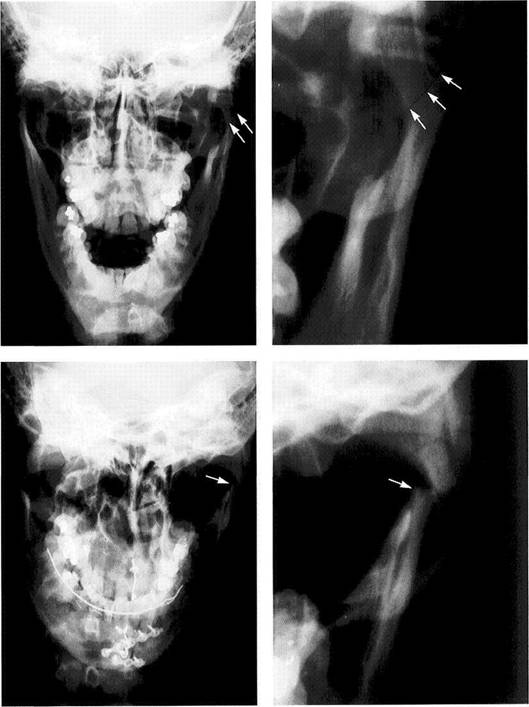

Intracapsular fracture

Left: Full frontal view radiograph showing an intracapsular fracture (arrows) in the left joint of a 17-year-old patient. The clinical symp­tom was pain in the temporo­mandibular joint region following a traumatic blow.

Right: Enlarged section of the left temporomandibular joint region. Here the line of disrupted continu­ity (arrows) can be seen more easi­ly. Depending upon the degree of dislocation, intracapsular fractures are treated either conservatively through intermaxillary fixation or treated surgically. After a surgical reduction, the fragments are im­mobilized with wire, miniscrews, or resorbable pins (Rasse et al. 1991). If untreated, an intracapsular frac­ture could lead to osteomyelitis (Sanders etal. 1977).

Fracture of the neck of the condyle

Left: Full facial view showing bilater­al fractures of the condylar process­es in a 38-year-old male patient. The paramedian fracture of the mandible has already been treated surgically.

Right: Enlarged section of the left temporomandibular joint region. In adults the fragments will usually heal by forming a bony union in the dislocated position (Choi 1996). Surgical repositioning of the con­dyle without fixation results in healing with a slight medial inclina­tion of the condyle. Subsequently, 48% of these condyles will show no alteration in their morphology (lizuka etal. 1998). Following condylar neck fractures in children, up to 77% will regain a normal physiological condylar shape through remodeling (Kellen-bergeretal. 1994).